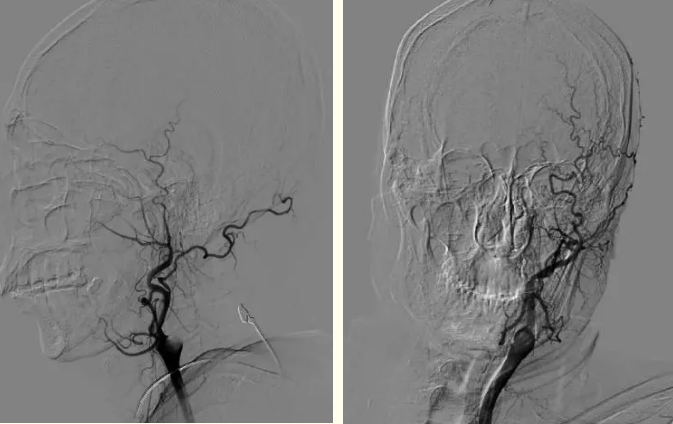

术中画面

我院副院长、神经内科专家刘忠锦副教授第一时间来到医院,卒中中心专家团队进入战时状态。考虑到病人既往房颤病史,经过综合评估,专家团队判断此次栓塞可能由于心源性栓子所致,静脉溶栓可能效果欠佳,建议行全脑血管造影并根据情况进行机械取栓治疗,否则病人很可能会有生命危险。经与家属充分沟通,神经介入小组立即启动,即刻急诊转运病人至导管室,此时距患者发病仅仅过去半小时左右。

全脑血管造影显示:左侧颈内动脉起始段闭塞

全脑血管造影显示患者左侧颈内动脉起始段闭塞,血栓负荷量大,手术难度较大,刘忠锦团队立即行机械取栓,经抽吸导管抽吸出大量血栓栓子,再给予支架取栓治疗,不断地努力后,终于打开了闭塞的大脑中动脉。造影显示右侧颈内动脉、大脑中动脉再通,观察10分钟后血流仍通畅,患者得救了,医护人员松了一口气。